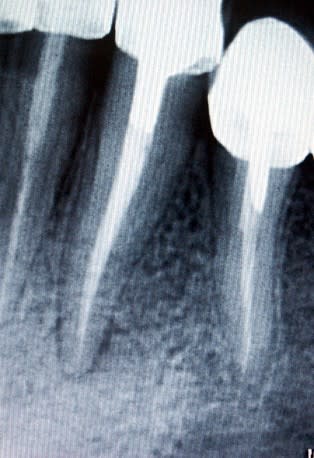

- Au fichier joint attaché, tu verras une dent où j'ai effectuée une reprise de traitement et que j'ai obturée avec un petit amalgame pour assurer l'étancheité. J'ai côté SC6. 6 mois après, la lésion étant presque disparue, j'ai fait un IC et une nouvelle couronne. Est ce que c'est toléré?

Bien sur, radios avant et après, de préférence avec le même angle pour comparer. Et conserve-les : on te les demandera un jour.